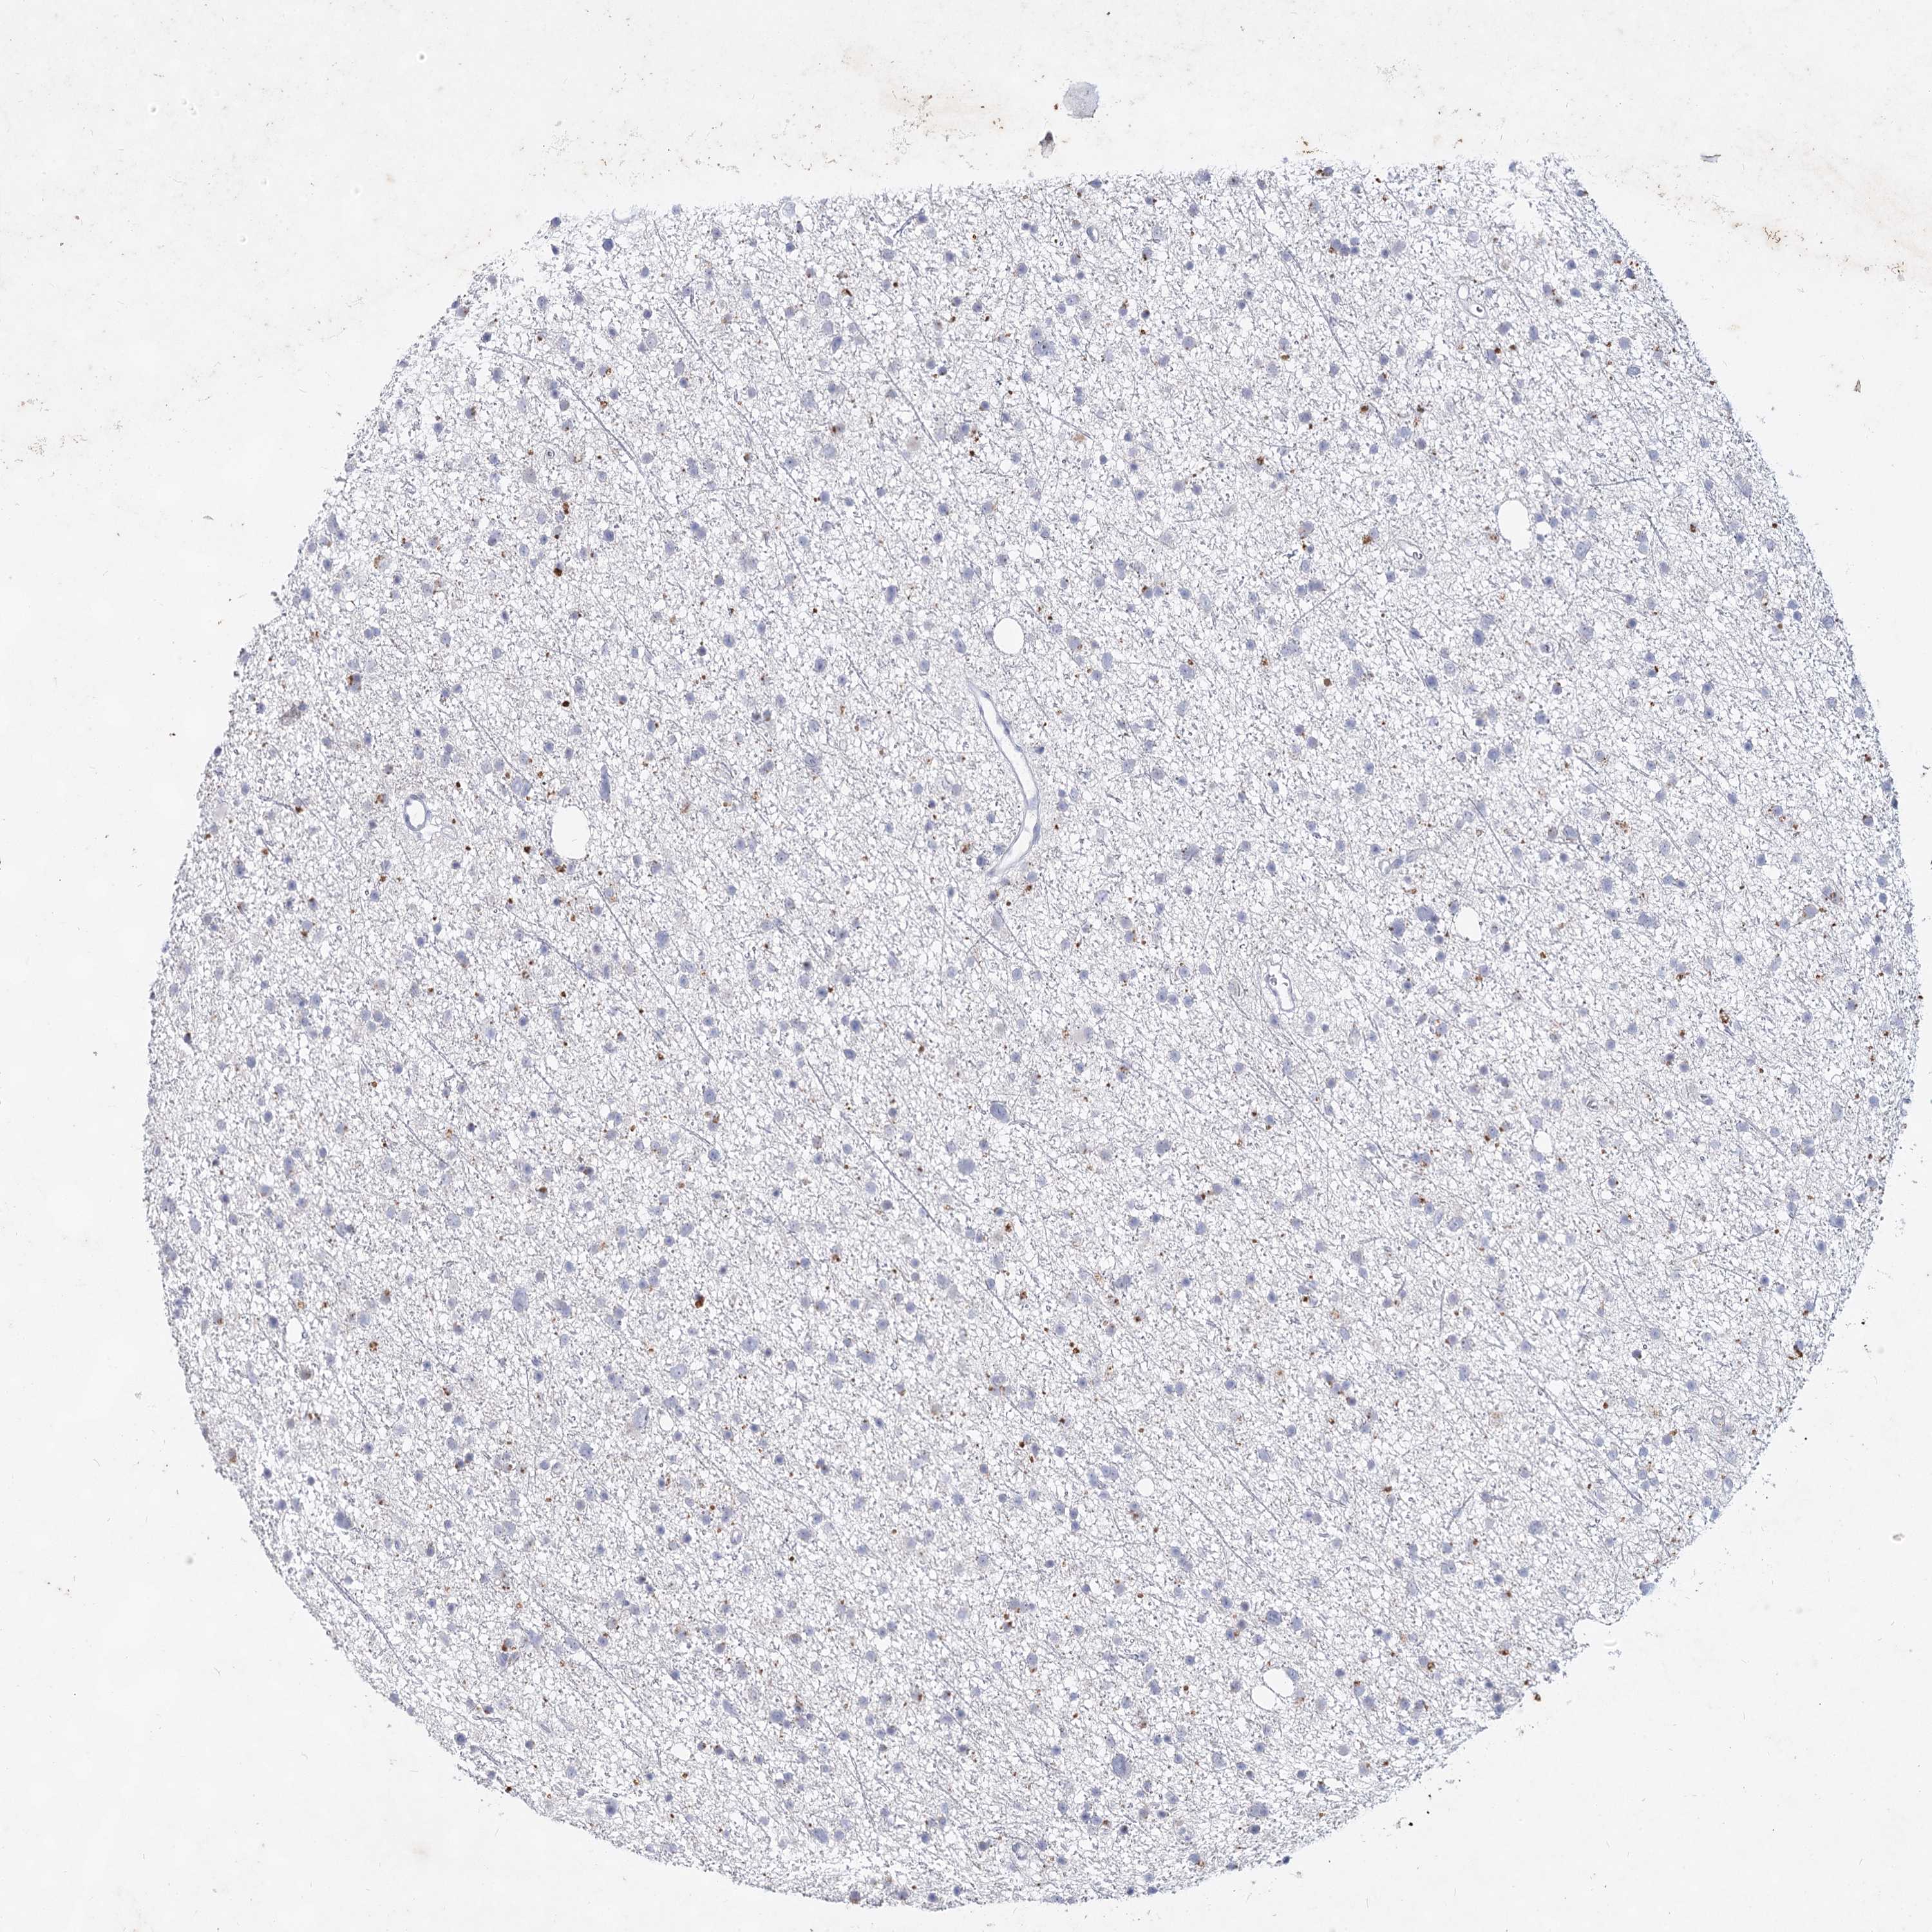

GLIOMA - Protein expressioni

A mouse-over function shows sample information and annotation data. Click on an image to view it in a full screen mode. Samples can be filtered based on level of antibody staining by selecting one or several of the following categories: high, medium, low and not detected. The assay and annotation is described here.

Note that samples used for immunohistochemistry by the Human Protein Atlas do not correspond to samples in the TCGA dataset.

Antibody stainingi

Antibody staining in the annotated cell types in the current human tissue is reported as not detected, low, medium, or high, based on conventional immunohistochemistry profiling in selected tissues. This score is based on the combination of the staining intensity and fraction of stained cells.

Each image is clickable and will lead to virtual microscopy that enables deeper exploration of all samples and also displays staining intensity scores, fraction scores and subcellular localization as well as patient and tissue information for each sample.

Antibody HPA038668

Antibody HPA038669

Staining

High

Medium

Low

Not detected

Intensity

Strong

Moderate

Weak

Negative

Quantity

>75%

75%-25%

<25%

None

Location

Nuclear

Cytoplasmic/membranous

Cytoplasmic/membranous,nuclear

Glioma, malignant, High grade

Glioma, malignant, Low grade

Glioblastoma, NOS